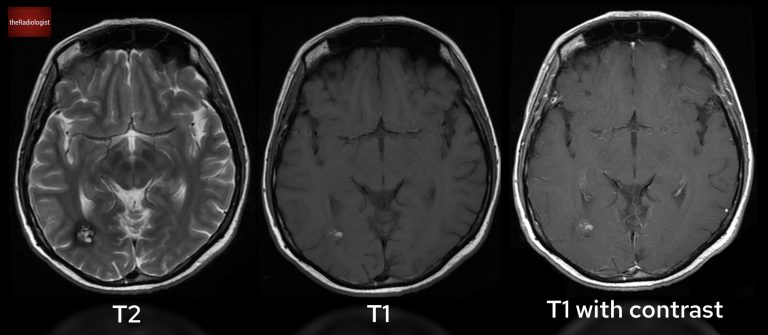

Given the unusual CT appearance, the patient underwent an MRI. Here’s what the MRI revealed:

• T2 Sequence:

• The lesion has a “popcorn” appearance, with a low-intensity rim: a hallmark feature.

• T1 Sequence:

• There’s high signal intensity, indicative of blood products.

• T1 post gadolinium contrast:

• The lesion shows no enhancement, helping us rule out certain neoplastic or inflammatory causes.

Have a look at T2 (left), T1 (centre) and T1 post gadolinium (right) sequences.